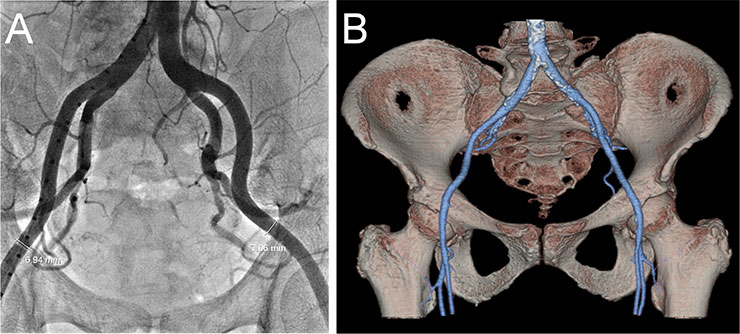

Figure 6

Screening of the iliofemoral arteries by fluoroscopy (A) and CT angiography (B).